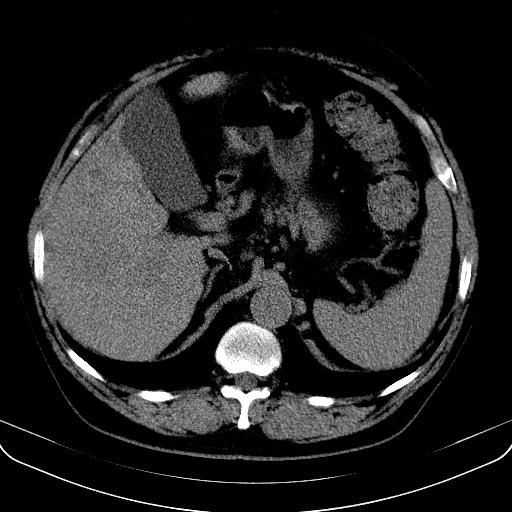

以下是引用jia119在2008-3-5 13:31:00的发言:[br]肝内多发片状低密度影,密度不均,我还是考虑肝ca可能,另肝内小囊肿,胆囊增大。

以下是引用形影不离在2008-3-5 12:18:00的发言:[br]肝硬化伴门脉高压征,肝内占位待排,增强再说.

以下是引用随光逐影在2008-3-5 21:11:00的发言:[br]肝硬化伴门脉高压(食管下段静脉曲张),肝癌不排除。建议:行ct增强扫描检查。

以下是引用同在2008-3-5 13:56:00的发言:[br]考虑肝癌可能性大,胆囊增大.